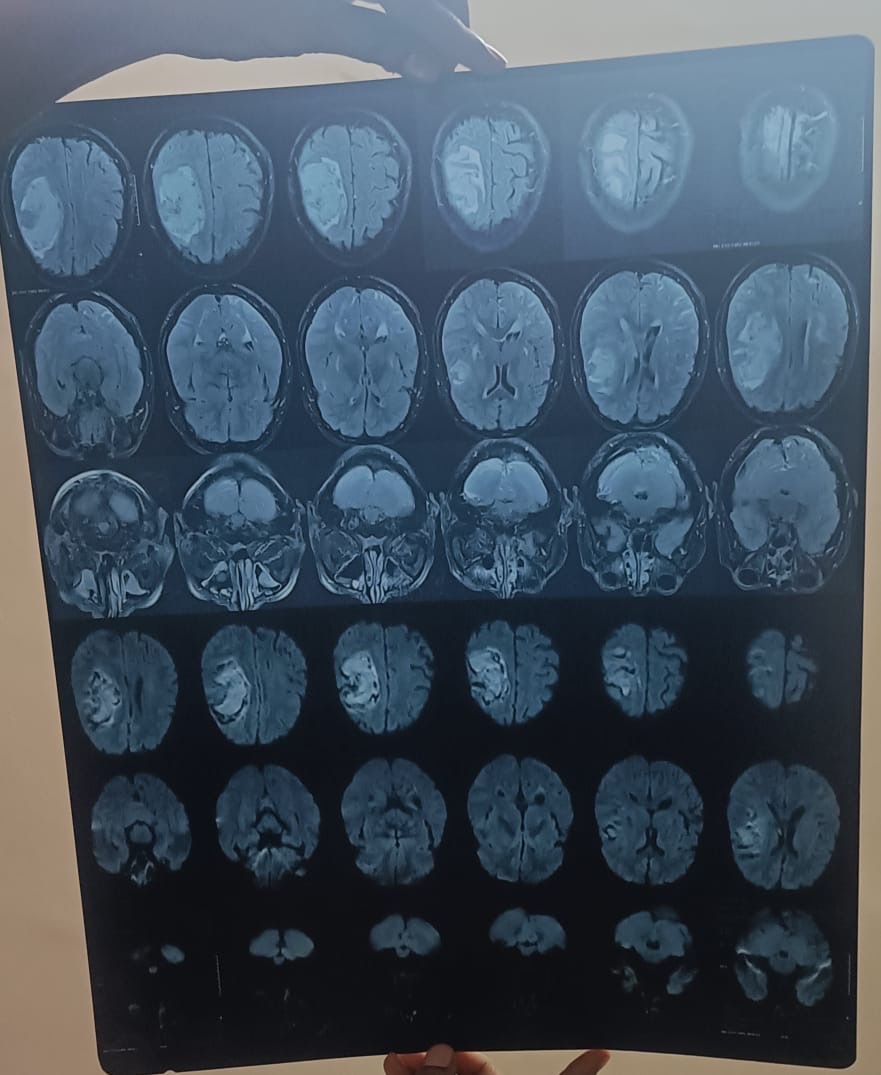

My name is Ajay Kumar Katkuri, resident of Fremont, CA. My father (age 60+) recently suffered a severe brain hemorrhage on the right side of his brain. The bleeding is large (over 5 cm), and it has extended into the brain’s ventricles, causing dangerous pressure and swelling. Doctors have confirmed a midline brain shift, which means urgent treatment is needed to prevent life-threatening complications or permanent disability.

Though he is conscious and recognizes us — which gives us hope — the condition is very serious and requires ICU care, potential surgery, and long-term rehabilitation.